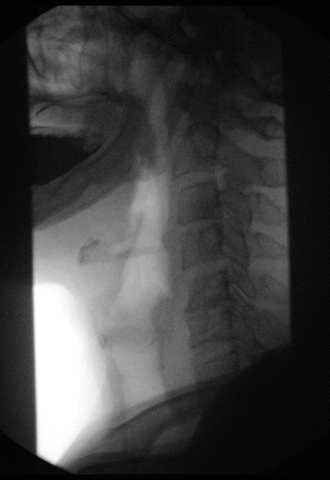

The image above is a barium (solution) swallow study and the resulting x-ray ‘movie’.